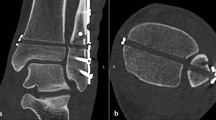

The establishment of testable models

Before the biomechanical experiment, all the muscles and tendons of the leg were removed, while the interosseous membrane and proximal/distal tibiofibular syndesmosis were kept intact (intact model). Soft tissues of the foot were left to enhance fixation into the machine. CT scans were performed to virtually make the 3D-printed guide template, and ensure that the bone tunnels of the syndesmotic fixation, including late anatomical fixation and malreduction fixation, do not interfere with each other. Then, all tibiofibular syndesmotic ligaments and the interosseous ligament were cut off to establish the syndesmotic separation model. A suture-button (Arthrex, Naples, USA) was used as the syndesmotic fixation (anatomical model). In order to establish the anterior malreduction model, the fibula was moved anteriorly by 1 cm, relative to the syndesmosis incisura (ant-malreduction model), or moved posteriorly by 1 cm to establish the post-malreduction model.

With the lateral fibular bone tunnels unchanged, the fibula samples were moved anteriorly and posteriorly by 1 cm to establish the ant-malreduction and post-malreduction groups, respectively. Then, a 3D-printed guide plate was used to re-fix the specimens, in order to form the malreduction model (ant-malreduction and post-malreduction groups). Afterwards, the same biomechanical tests were performed, and data were collected as the ant-malreduction and post-malreduction groups. Figure 1 presents the experimental protocol, Fig. 2 shows the experimental setup, and Fig. 3 shows the CT scan of three bone tunnels made by template.